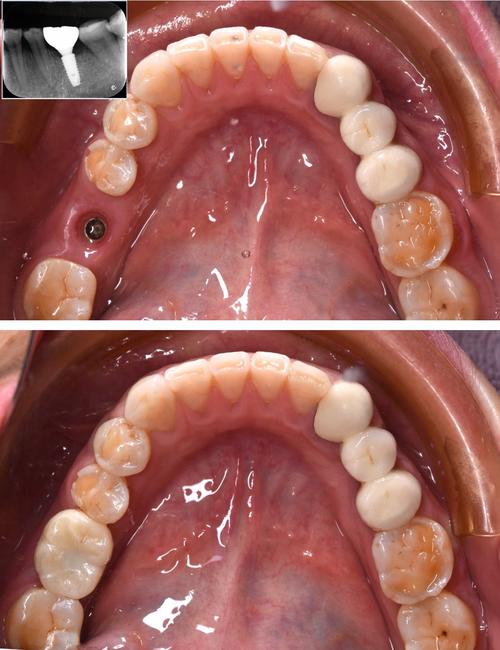

案例1:轻度牙周炎患者(牙周袋≤4mm,牙槽骨吸收≤根长1/3)

患者情况:42岁男性,右上第一磨牙缺失3个月,余牙牙龈轻微出血,牙周探诊深度3-5mm,牙槽骨高度约根长2/3,无松动。

牙周治疗:行全口龈上洁治+龈下刮治,去除牙菌斑和牙石,配合局部药物治疗(如米诺环素凝胶),1个月后复查牙周指标稳定。

种牙方案:选择常规种植体(直径4.0mm,长度10mm),微创植入,术后3个月完成上部修复。

效果:种植体骨结合良好,无松动,牙龈形态正常,咀嚼功能恢复。